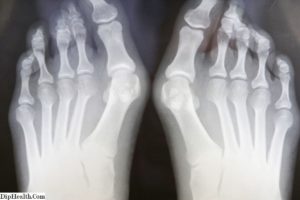

На рентгене можно четко увидеть окостеневшее тело экзостоза.

Остеохондрома обнаруживается случайно во время осмотра. Вообще экзостоз диагностировать довольно просто. Нарост прощупывается под кожей. Образование можно четко увидеть на рентгеновском снимке.

Чаще всего заболевание выявляется случайно во время прохождения рентгенологического исследования. Без рентгена диагностика практически невозможна.

Проведение этого вида исследования позволяет сказать о числе и форме новообразований, их размерах и развитии. В то же время, необходимо учитывать, что хрящевой налет, который покрывает нарост, на снимке не виден.

Поэтому настоящие размеры опухоли всегда больше, чем кажутся.

Рентгенография дает полное представление о наличии экзостозов, их количестве, размерах, расположении, форме, строении, этапе развития и т.д. Рентгенограмма не показывает наружный хрящевой слой, поэтому реальные размеры наростов всегда больше, чем видны.